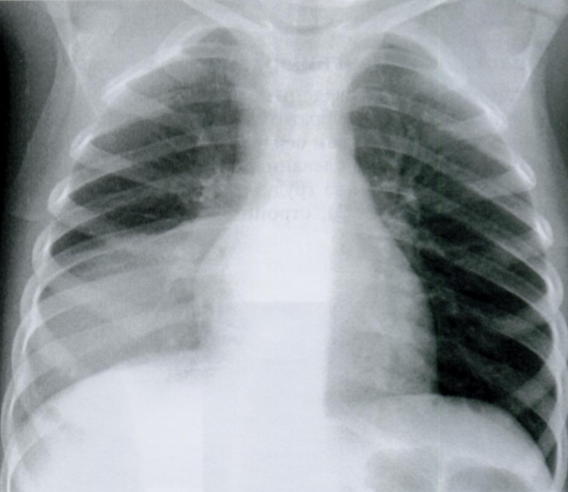

Rx лежа и на выдохе (обратите внимание на положение верхушек легких, отмечены стрелками)

Если мы выполним Rx органов грудной клетки на выдохе, то из-за высокого стояния куполов диафрагмы, сердце будет казаться приподнятым и расширенным, а сосуды легких сдавлены и полнокровны.